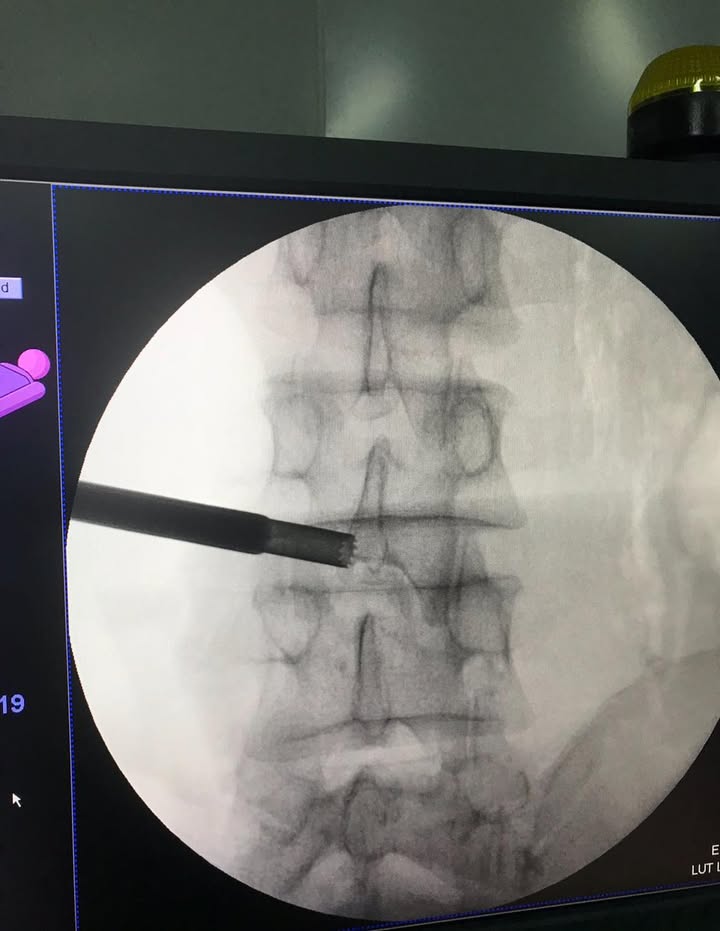

PS 附上大陸目前執行針刀最新的方式

動態C型壁定位椎間孔針刀療法